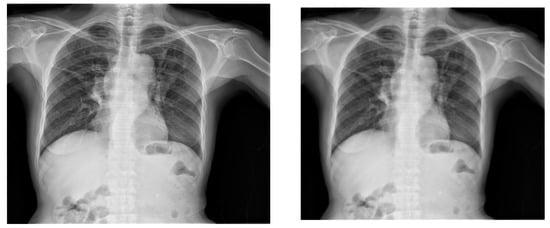

When it comes to X-ray images, rotation is a commonly used augmentation technique, as shown in Figure 5 and Figure 6. To apply a clockwise and anticlockwise rotation transformation to the X-ray image by 5 degrees, the Image library was used. The rotation also had to persist in the respective bounding box, which was also performed with the Image library.

Similarly, scaling is also a frequently employed augmentation technique, as illustrated in Figure 7. To implement a scaling transformation with a scaling factor of 0.8, the Image library was utilized. This involved adjusting the size of the X-ray image uniformly to 80% of its original dimensions. Notably, the scaling transformation was extended to maintain consistency within the corresponding bounding box; a process seamlessly executed using the Image library. This ensures that the scaling effect persists coherently across both the X-ray image and its associated bounding box.

Figure 5. Original X-ray (left image) and the output of the application of anticlockwise rotation of the X-ray images by 5 degrees (right image).

Information 14 00655 g005

Figure 6. Original X-ray (left image) and the output of the application of clockwise rotation of the X-ray images by 5 degrees (right image).

Information 14 00655 g006

Figure 7. Original X-ray (left) and 0.8 scaled X-ray (right).

Information 14 00655 g007

Figure 8. Original X-ray (left) and horizontal flipping of the X-ray (right).

Information 14 00655 g008